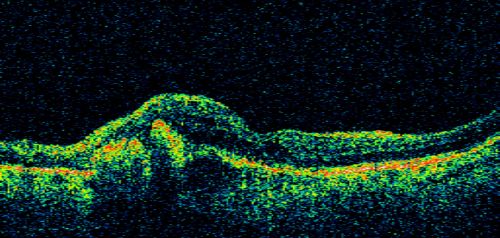

AMD - Wet - Fibrovascular Hemorrhagic PED - Occult CNVM

87-year-old woman for one month OS: 20/60 Fibrovascular PED and Hemorrhage